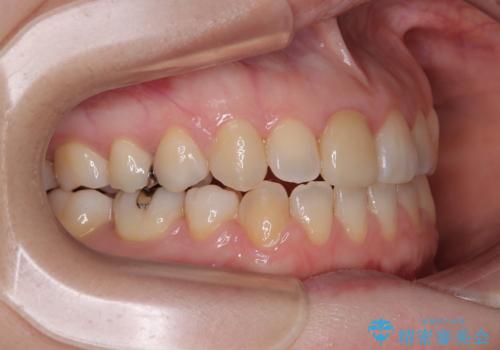

- 学生時代に行った抜歯矯正の後戻りで、隙間ができてしまったことを気にして来院された患者様です。

マウスピース矯正を検討されていましたが、後戻りの隙間が非常に大きく、奥歯を前方に移動させる必要があるため、ワイヤー装置にて矯正治療を行うこととしました。

舌の突出癖が非常に強く、その影響で隙間ができてしまったので、舌のトレーニングをしっかりと行っていただきました。

上顎歯列は歯の移動量が少なかったため、セラミッククラウンは装置を装着せずに治療を終えることができました。